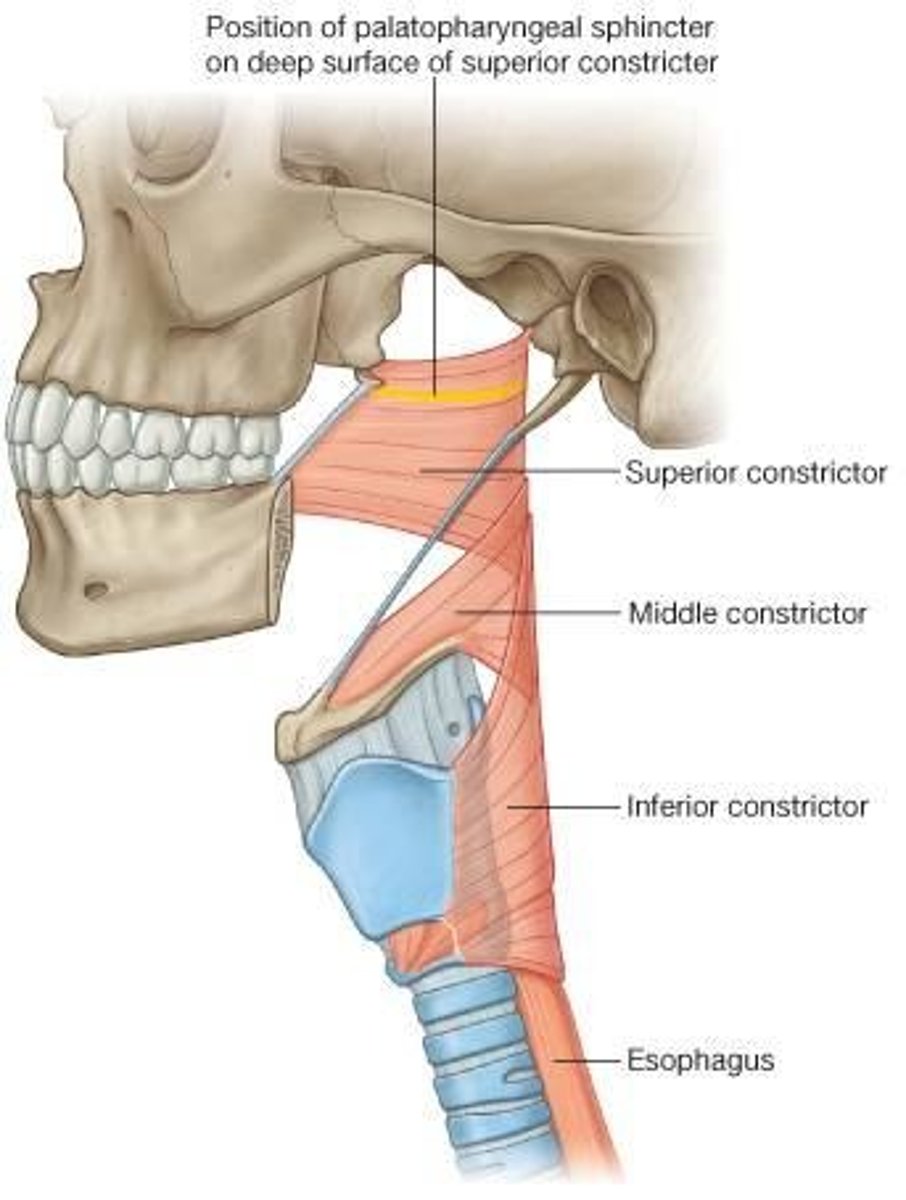

Superior Constrictor Description

Weakest, but most complex of the three

Forms nasopharyngeal and upper

oropharyngeal walls

Origin - sphenoid, mandible, pterygomandibular ligament

Course - posterior, then medial

Insertion - midline raphe

Action - may contribute to velopharyngeal closure by moving posterior wall of pharynx

anteriorly

Middle Constrictor Description

Somewhat fan shaped

Origin - hyoid bone

Course - fan out posteriorly and medially

Insertion - midline raphe

Action - reduce diameter of pharynx

Inferior Constrictor -

Thyropharyngeus Description

Inferior Constrictor consists of the

Thyropharyngeus and the Cricopharyngeus

Inferior Constrictor is thickest and strongest of constrictor muscles

Thyropharyngeus is the majority of the Inferior Constrictor

Origin -thyroid cartilage

Course - fans out posteriorly and medially

Insertion - midline raphe

Action - reduce diameter pharynx